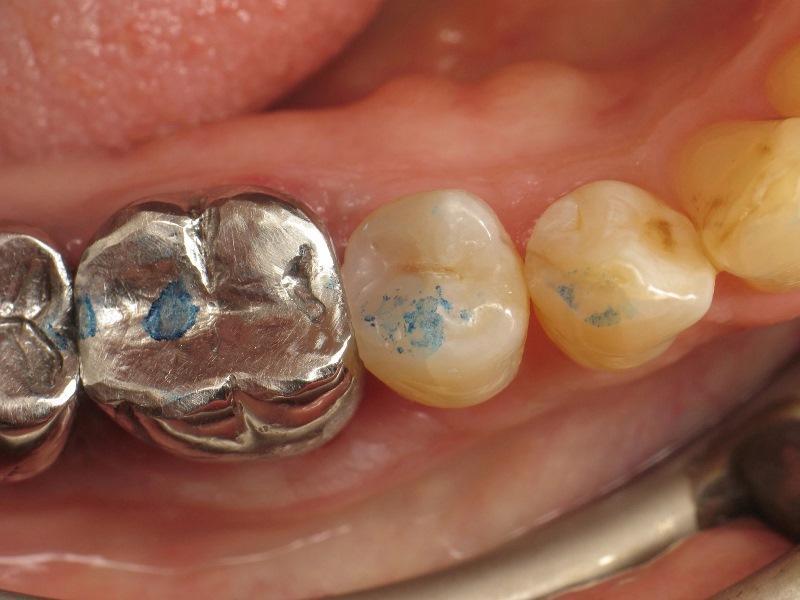

Фото 1. Премоляр с кариесом II класса.